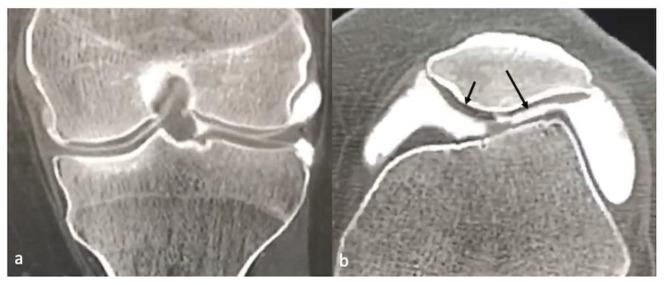

软骨及软骨损伤的影像学:综述

Imaging of Cartilage and Chondral Defects: An Overview.

A healthy articular cartilage is paramount to joint function. Cartilage defects, whether acute or chronic, are a significant source of morbidity. This review summarizes various imaging modalities used for cartilage assessment. While radiographs are insensitive, they are still widely used to indirectly assess cartilage. Ultrasound has shown promise in the detection of cartilage defects, but its efficacy is limited in many joints due to inadequate visualization. CT arthrography has the potential to assess internal derangements of joints along with cartilage, especially in patients with contraindications to MRI. MRI remains the favored imaging modality to assess cartilage. The conventional imaging techniques are able to assess cartilage abnormalities when cartilage is already damaged. The newer imaging techniques are thus targeted at detecting biochemical and structural changes in cartilage before an actual visible irreversible loss. These include, but are not limited to, T2 and T2* mapping, dGEMRI, T1ρ imaging, gagCEST imaging, sodium MRI and integrated PET with MRI. A brief discussion of the advances in the surgical management of cartilage defects and post-operative imaging assessment is also included.

摘要

健康的关节软骨对关节功能至关重要。软骨缺损,无论是急性还是慢性的,都是发病的重要原因。本综述总结了用于软骨评估的各种成像方式。虽然X线片不敏感,但仍广泛用于间接评估软骨。超声在检测软骨缺损方面显示出前景,但由于可视化不足,其在许多关节中的效果有限。CT关节造影有潜力评估关节内部紊乱以及软骨情况,尤其是在有MRI禁忌证的患者中。MRI仍然是评估软骨最受欢迎的成像方式。传统成像技术能够在软骨已经受损时评估软骨异常。因此,更新的成像技术旨在在实际可见的不可逆损失之前检测软骨的生化和结构变化。这些技术包括但不限于T2和T2*映射、双对比增强MRI(dGEMRI)、T1ρ成像、糖化学交换饱和转移(gagCEST)成像、钠MRI以及PET与MRI的联合成像。本文还简要讨论了软骨缺损手术治疗的进展以及术后成像评估。